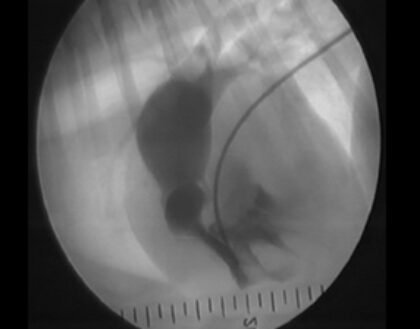

Die Pulmonalstenose zählt weltweit zu den häufigsten angeborenen Herzfehlern beim Hund und spielt daher in der kardiologischen Praxis eine wichtige Rolle. In der Aufarbeitung dieser Patienten spielt neben Anamnese, klinischer Untersuchung, Röntgen und EKG die Echokardiographie die wesentlichste Rolle. Eine exakte Klassifizierung und Quantifizierung dieser Tiere ist essenziell, um ein adäquates Therapieverfahren zu ermitteln. Insbesondere eine Abgrenzung gegen andere Arten einer rechtsventrikulären Ausflusstraktobstruktion wie dem double chamber right ventricle ist wichtig und kann mitunter sehr anspruchsvoll sein.

Die Quantifizierung des Schweregrades geht primär über die echokardiographische Erfassung des Druckgradienten, sollte aber mit anderen Verfahren verifiziert werden. Das Ergebnis der Untersuchung zieht dann eine individuelle Therapie-Entscheidung nach sich. In diesem vetinar lernen Sie Schritt für Schritt die Aufarbeitung der Patienten mit einer Pulmonalstenose.